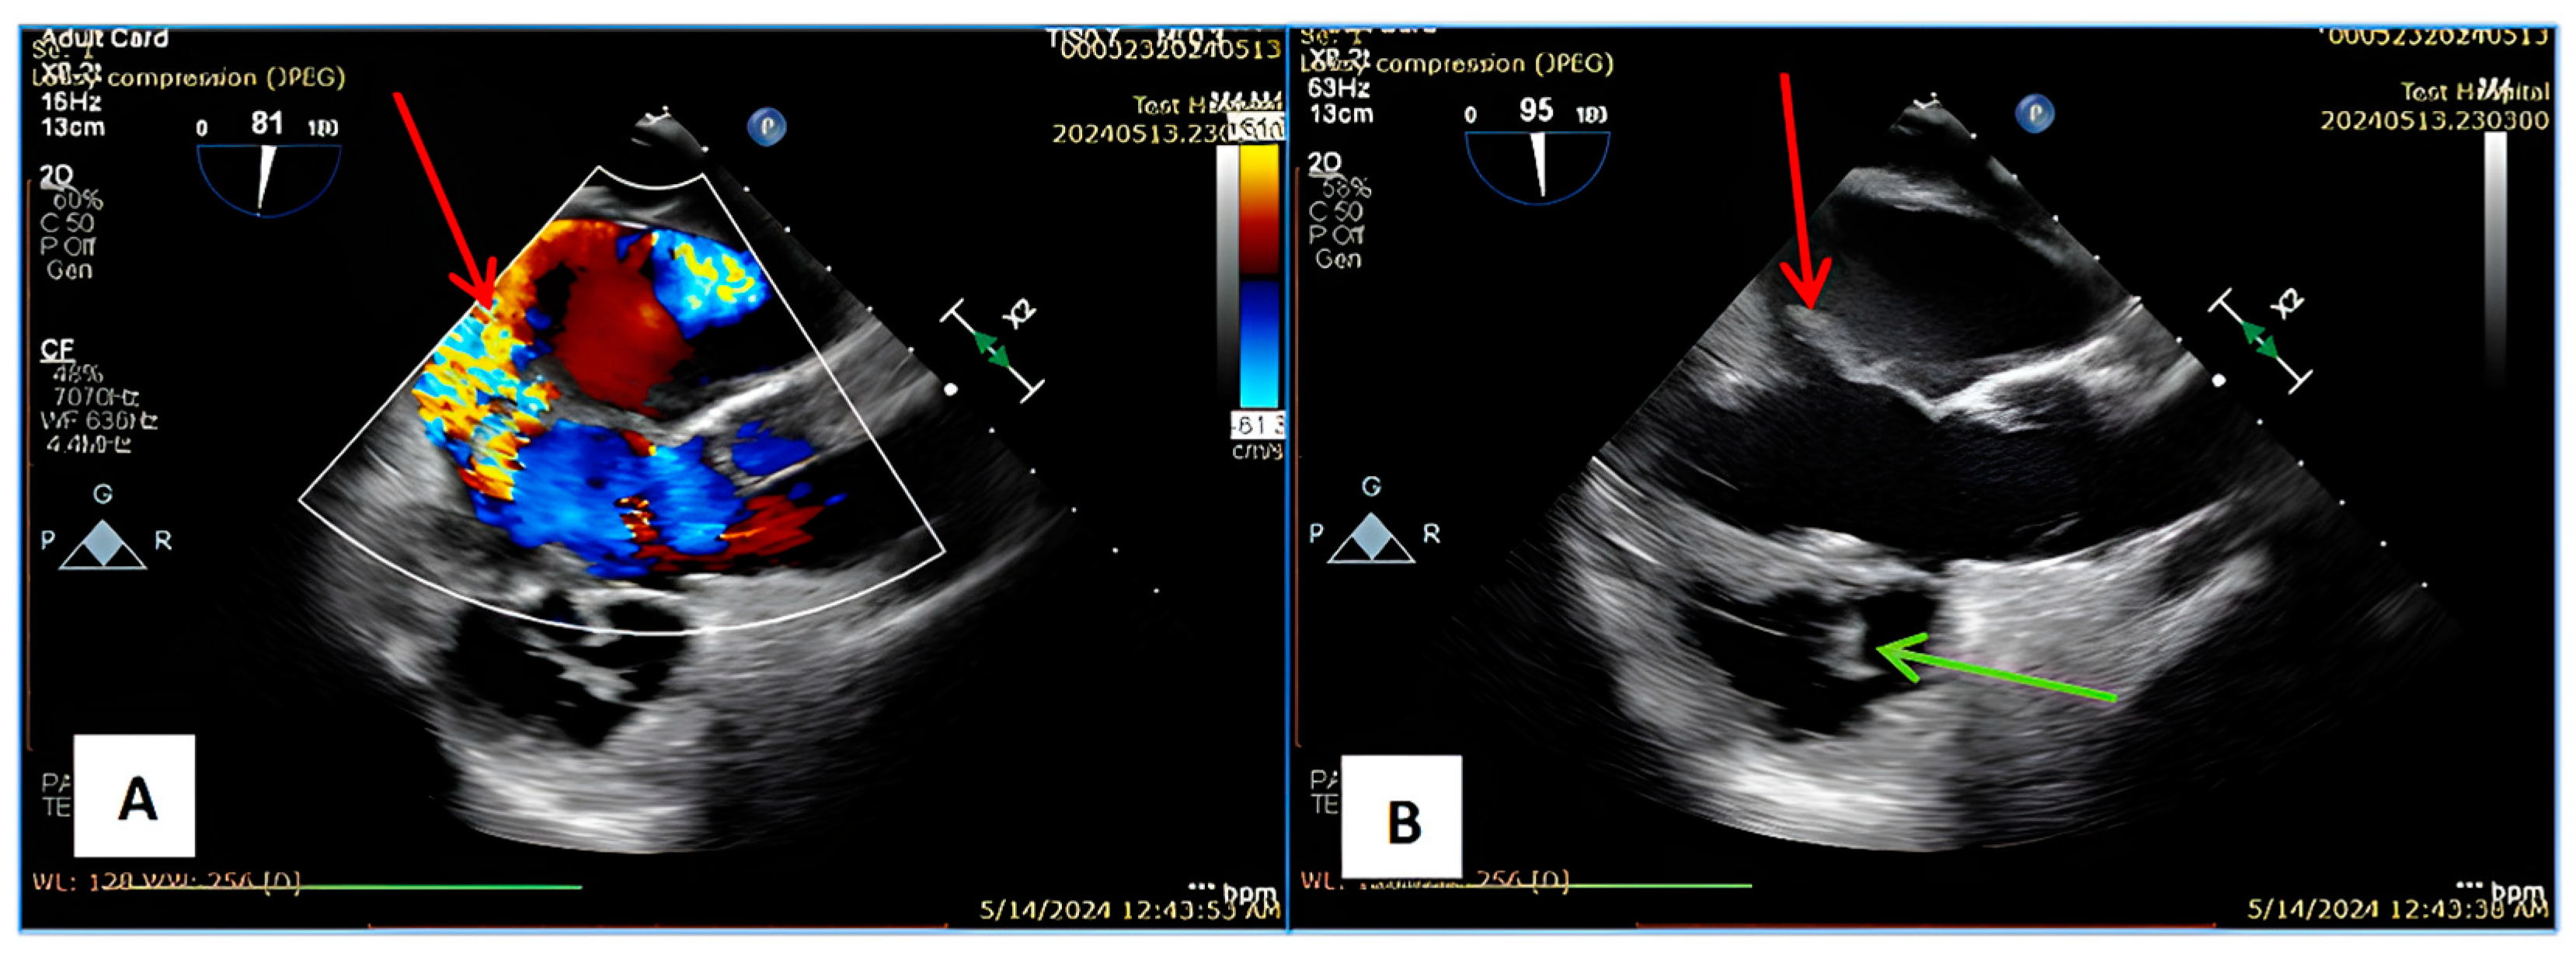

2. Case Report